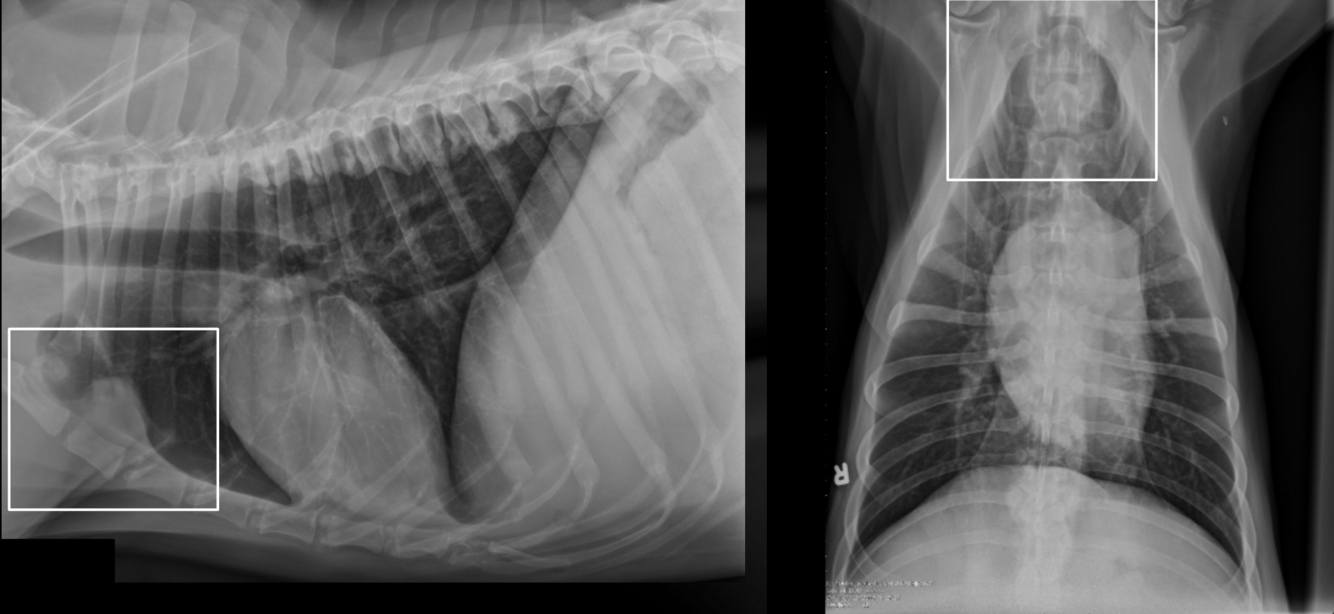

What is shown in these images?

A

generalized lymphadenopathy:

-widening of mediastinum

-deviation of mainstem bronchi